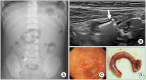

Ingestion of foreign bodies (FBs) is a common phenomenon among young children. Plain radiography is the first step diagnostic modality to detect the radio-opaque FBs. And computed tomography has been recommended by several guidelines as useful modalities for diagnosing ingested FBs. However, there is a risk of radiation exposure, making it burdensome to use in asymptomatic patients. Ultrasound (US) is not a commonly used technique for diagnosing ingested foreign bodies. However, US can provide real-time imaging with good resolutions without radiation exposure in pediatric patients. Herein, we report two pediatric cases of metallic foreign body ingestion that were successfully diagnosed using US for localizing foreign bodies. This study indicates that US may be used as an alternative method for detecting the localization of metallic foreign bodies in the gastrointestinal tract without exposure of radiation, particularly in pediatric patients.